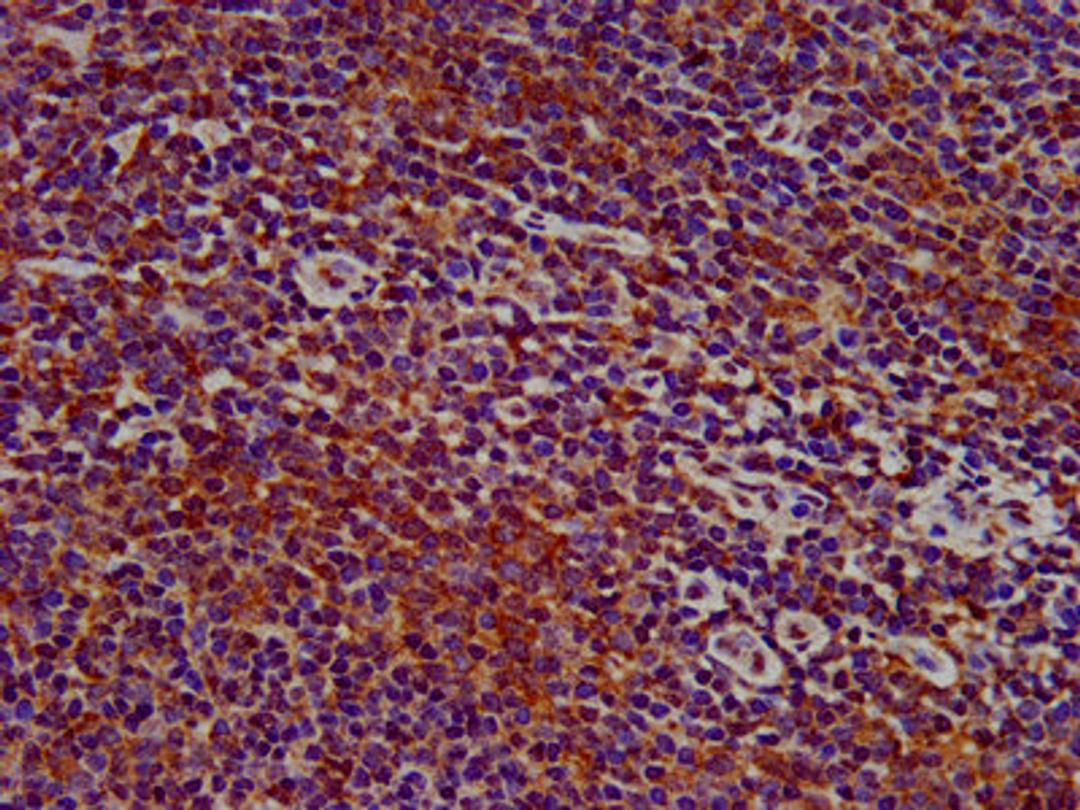

IHC image of CSB-PA842706LA01HU diluted at 1:400 and staining in paraffin-embedded human lymph node tissue performed on a Leica BondTM system. After dewaxing and hydration, antigen retrieval was mediated by high pressure in a citrate buffer (pH 6.0). Section was blocked with 10% normal goat serum 30min at RT. Then primary antibody (1% BSA) was incubated at 4°C overnight. The primary is detected by a biotinylated secondary antibody and visualized using an HRP conjugated SP system.